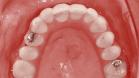

Damit ein Implantat langfristig erfolgreich ist, müssen einige Bedingungen erfüllt sein: